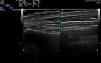

Upper trace, epidermis; middle trace, dermis; lower trace, subcutaneous cellular tissue. Lesional skin (left): cleft in the epidermis seen as a double hyperechoic band with a hypoechoic central area on a somewhat hypoechoic dermis (possible artifact secondary to variability in epidermal thickening). Upper band: undulation that alternates between more hyperechoic areas (convex) and more hypoechoic areas (concave). Healthy skin (right): epidermis with no abnormalities in the form of a fine homogeneous hyperechoic band.

We report the case of a 38-year-old woman (skin type V) with a history of tricuspid and mitral regurgitation who had undergone pulmonary bilobectomy for atypical carcinoid tumor. She was taking oral contraceptives. She attended our center with a flare-up of pruriginous lesions on her hands and forearms that had first appeared 1 year previously. The lesions appeared every month and did not remit completely between flare-ups, although they did improve with medium-potency topical corticosteroids. She reported no lesions at other sites and denied having had concomitant symptoms. Physical examination revealed poorly defined, apparently residual erythematous-brownish macules on the anterior and lateral surfaces of the wrists. Multiple hyperpigmented papules with a shiny surface measuring between 1 mm and 3mm in diameter were observed on the radial surface of the first finger of both hands and on the palmar creases. These alternated with flesh-colored papules with a lichenoid appearance on the adjacent skin and were distributed symmetrically (Fig. 1). An ultrasound scan (Esaote, MyLabClass C with a 22-MHz transducer) of the affected area on the lateral surface of the wrist revealed epidermal thickening in the form of a cleft, which was observed as double hyperechoic band with a hypoechoic central area. The upper band was characterized by undulations that varied between more hyperechoic areas (convex) and more hypoechoic areas (concave) (Fig. 2). Ultrasound revealed a certain degree of hypoechogenicity in the dermis that was interpreted as an artifact resulting from epidermal thickening using the 22-MHz transducer. The suspicion of lichen nitidus compared with elastic fiber abnormality led us to perform a biopsy of the ultrasound lesion and to prescribe clobetasol cream. Histopathology revealed a compact area of orthokeratotic hyperkeratosis resting on a slight epidermal depression with mild hypergranulosis in the epidermis (Fig. 3). No inflammation or other significant histopathological abnormalities were observed. Orcein staining did not reveal elastorrhexis. Therefore, the findings were compatible with focal acral hyperkeratosis (FAH)–type marginal papular acrokeratoderma. At subsequent visits, the patient reported a lack of improvement with her daily high-potency corticosteroid and even mentioned the appearance of additional lesions; consequently, we recommended a switch to mometasone and calcipotriol cream.

In addition to the histology findings, we reported the ultrasound characteristics of the condition, which involved a specific epidermal cleft with marked changes in echogenicity and no abnormalities in the dermis. No abnormalities of the healthy skin were observed (the marked difference in the thickness of the epidermis can be seen in Fig. 3). To date, diagnosis of FAH has been based on characteristic symptoms with consistent demographic data and a potentially compatible family history, as well as on the absence of dermal abnormalities in histology. The finding of the ultrasound characteristics used in the differential diagnosis8 of FAH (acrokeratoelastoidosis itself, plane warts, acrokeratosis verruciformis, punctate porokeratosis, punctate palmoplantar keratoderma, palmoplantar lichen planus, and juvenile elastoma) could be essential for determining the role of ultrasound in the differential diagnosis of these conditions. The main limitation is the low number of cases and, therefore, the difficulty in matching with similar clinical presentations in the various conditions that manifest as palmoplantar keratoderma. There is no evidence to support treating FAH, which often proves to be ineffective: given the absence of symptoms, not treating is a reasonable option.9